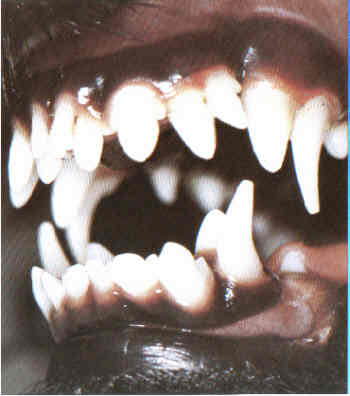

Milchzähne

Wenn Milchzähne nicht rechtzeitig ausfallen, so bildet sich mit den nachkommenden bleibenden Zähnen eine doppelte Zahnreihe. Solche Milchzähne behindern die bleibenden Zähne und müssen gezogen werden.